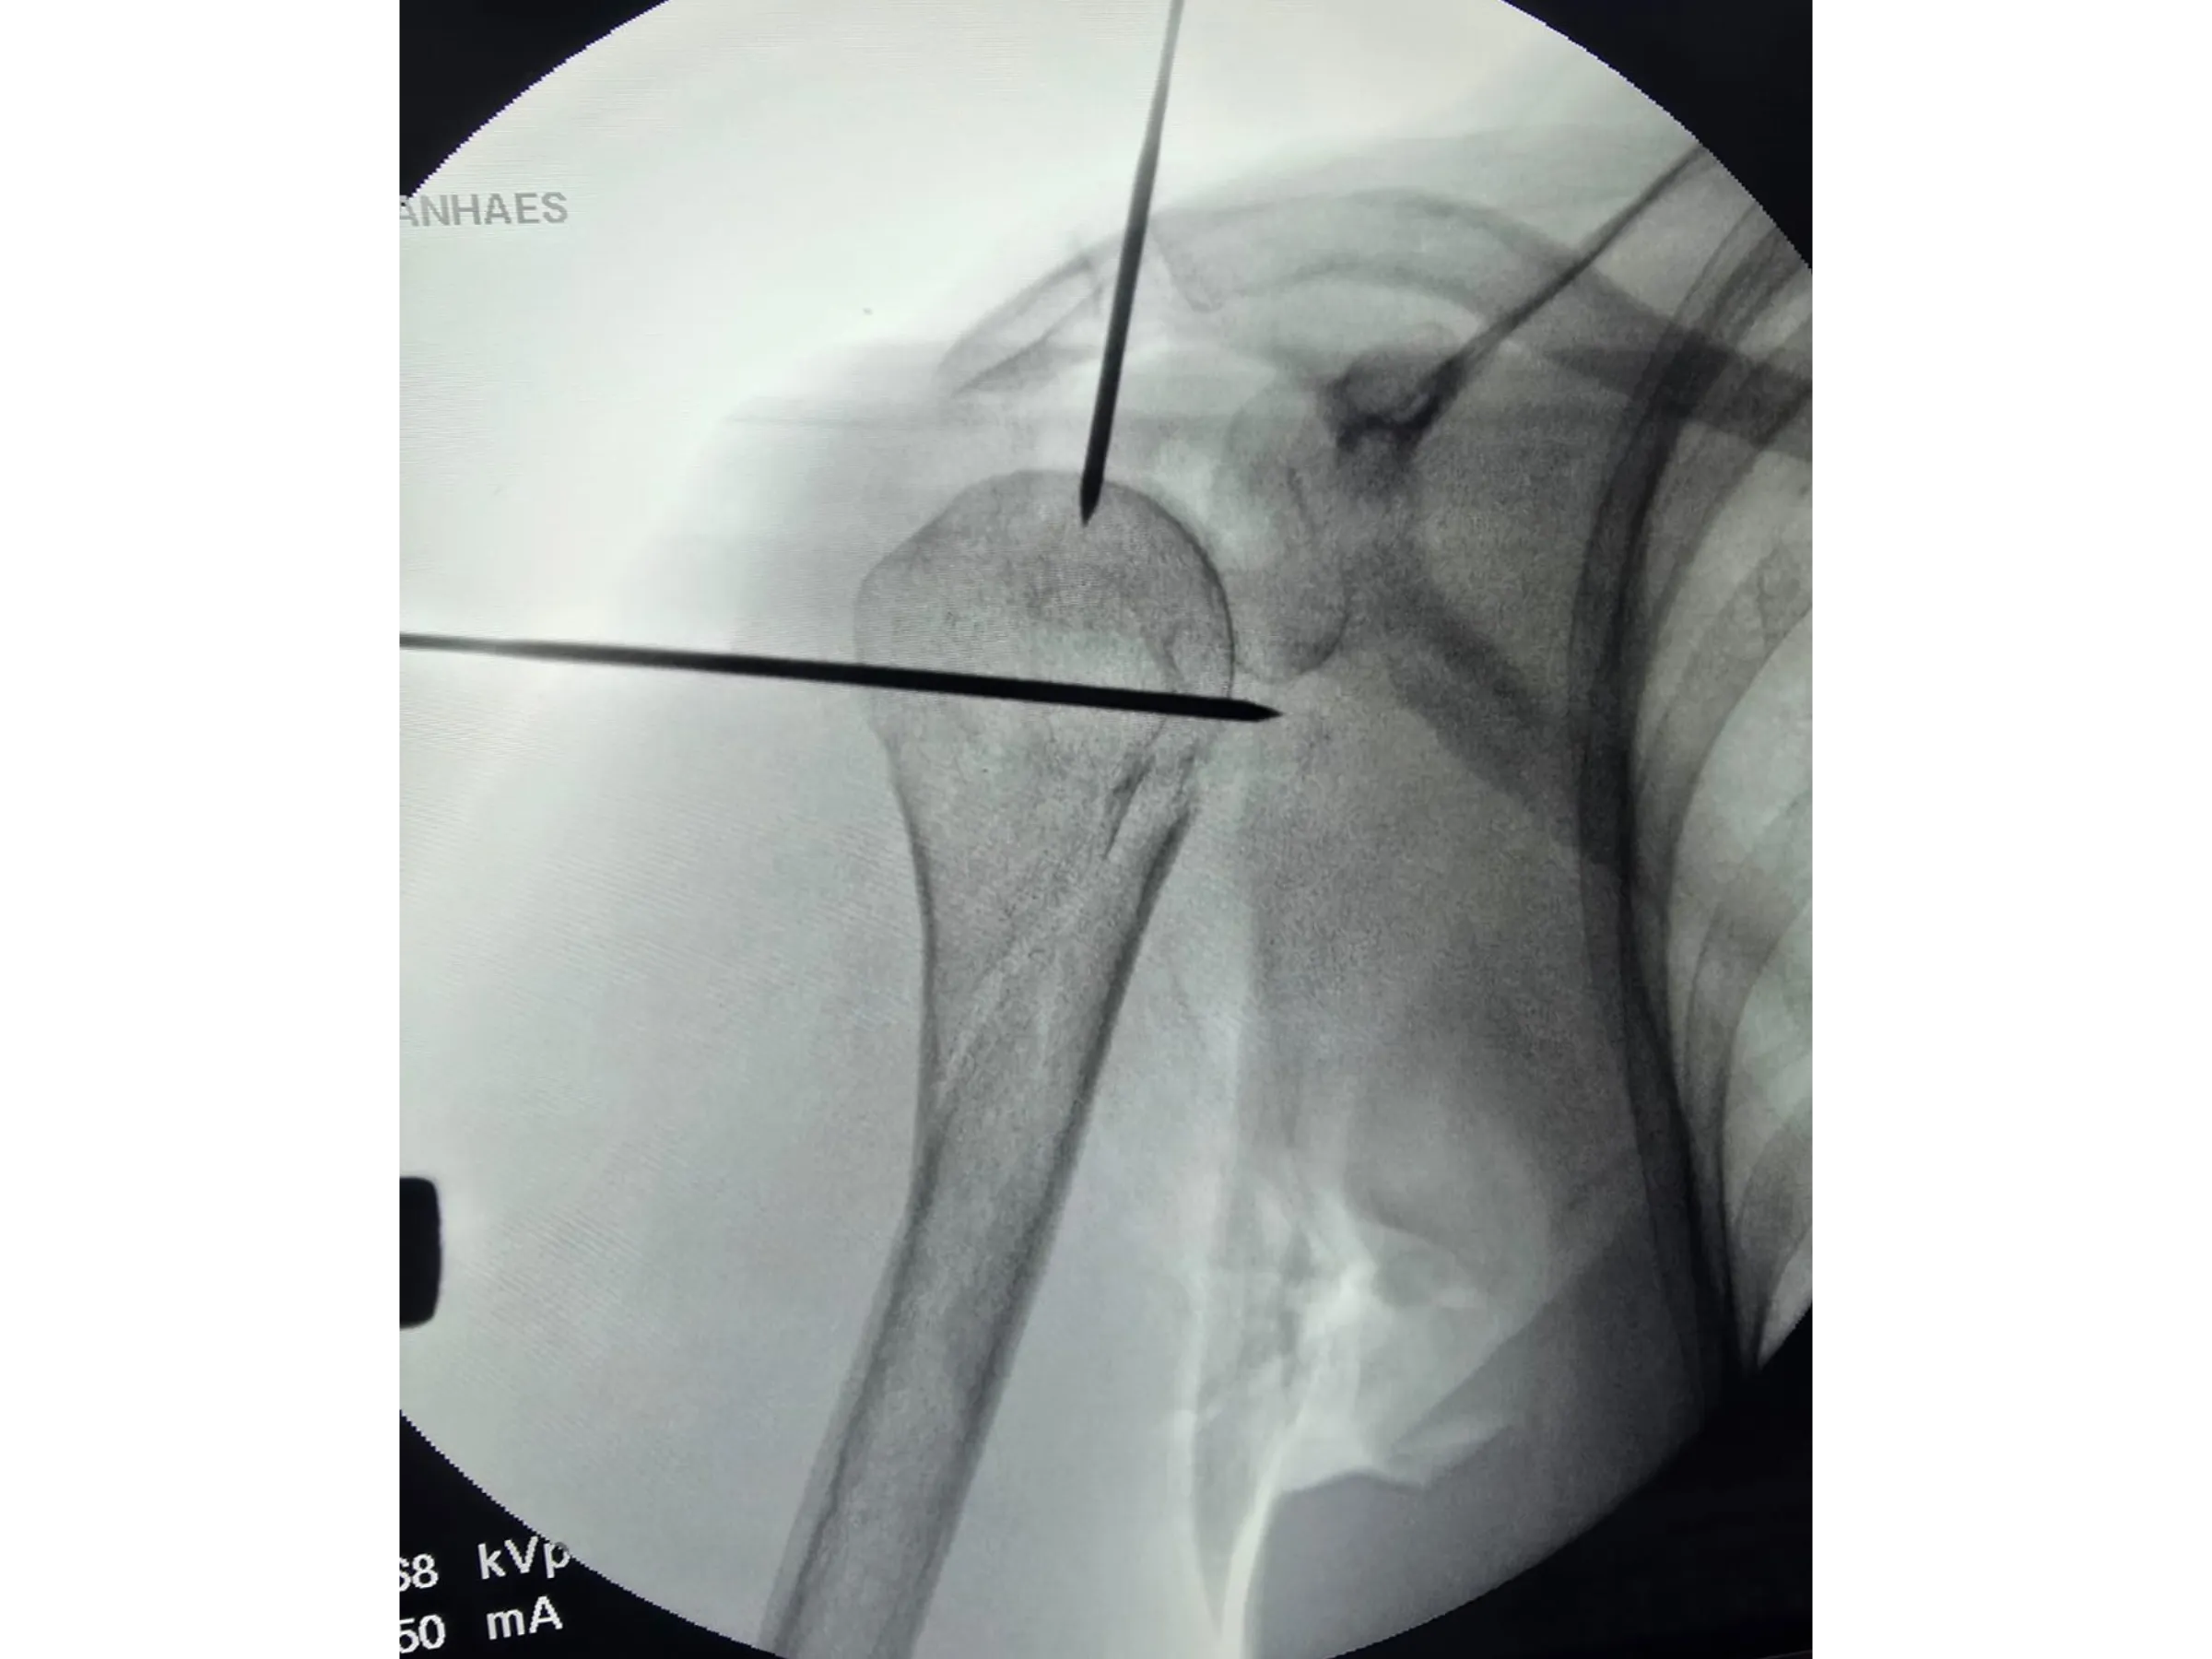

- Anatomical marking and guide wire insertion with radiographic control.

- Kirschner wire joystick-type manipulation.

- Precise Radiographic Marking: Use of Kirschner wires and dermography for sagittal alignment.

- Joystick for Humeral Head Alignment: Safe manipulation for correcting the angle and centering of the entry point.

- Rigorous Fluoroscopic Control: Anteroposterior and lateral images to ensure parallelism and precision of the implants.